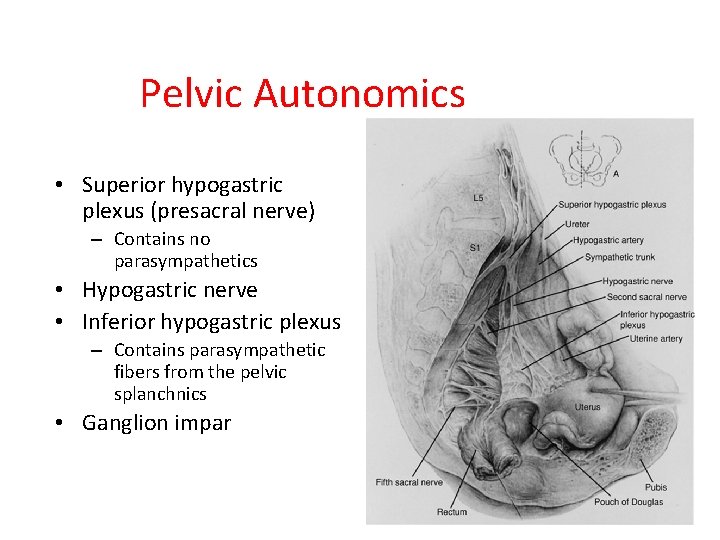

Pelvic Autonomics • Superior hypogastric plexus (presacral nerve) – Contains no parasympathetics • Hypogastric nerve • Inferior hypogastric plexus – Contains parasympathetic fibers from the pelvic splanchnics • Ganglion impar